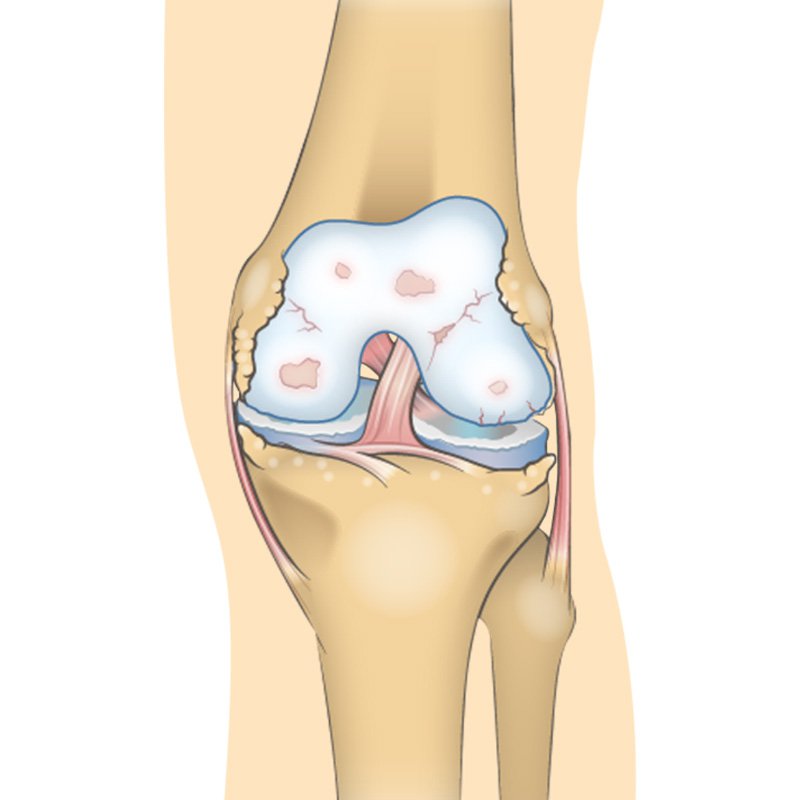

Over time osteoarthritis affects the bone cartilage and synovial fluid of the knee. With moderate knee OA, changes in the joint are much more evident the cartilage surface between the bones has begun to a road narrowing the gap between the femur and the tibia. hyaluronic acid which helps synovial fluid lubricate the joint is now becoming less viscous elastic and concentrated. Osteoarthritis often affects the sub-chondral bone Located just underneath the cartilage. Some contraband provides hydration and oxygen to the cartilage. Osteo fights may increase in number and size making the bone rougher. All these factors combined to make joint pain more severe and long-lasting both with movement and at rest. OA conditions worsened dramatically the joint spaces become far narrower causing more rapid and severe destruction of the cartilage in the knee becomes inflamed and sore. Synovial fluid is decreased increasing friction and pain during movement. Osteo fights continue to develop bone moves against bone not cartilage mobility activities of daily living and quality of life are severely impacted.”

Frequent pain during movement, joint stiffness will also be more present, especially after sitting for long periods and in the morning. The cartilage between the bones shows obvious damage, and the space between the bones is getting smaller.